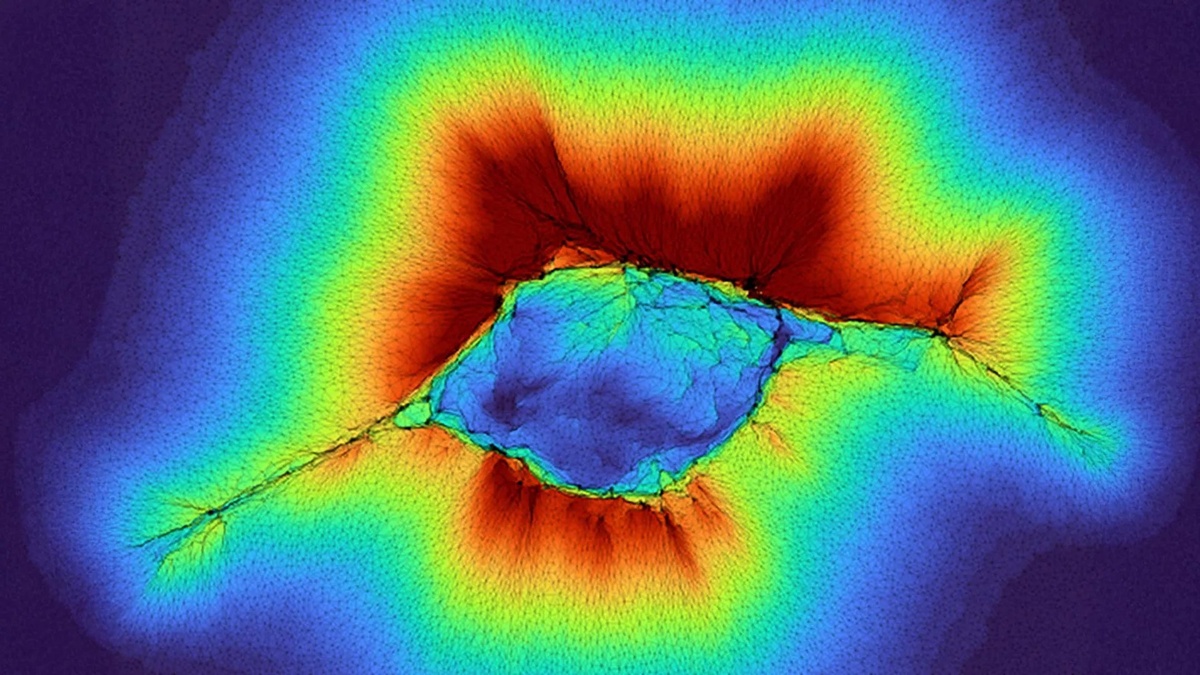

В основе процесса лежит взаимодействие клеток с внеклеточным матриксом, особенно с волокнами коллагена. Клетка тянет и деформирует эти волокна, за счёт чего как бы передаёт механический сигнал дальше в ткань и получает информацию о том, что находится глубже: более жёсткий участок, более мягкая ткань или другая структура поблизости.

Главное открытие новой работы в том, что коллектив клеток действует значительно мощнее одиночной клетки. Когда эпителиальные клетки собираются вместе и начинают двигаться как единая группа, они создают существенно большую механическую силу. За счёт этого волокнистый коллаген деформируется глубже, и клетки получают информацию уже с расстояния до 100 микрон.

По сути, речь идёт о коллективном механическом «зондировании» среды. Именно совместная работа делает клеточную группу гораздо более чувствительной к структуре окружающих тканей, чем любую клетку по отдельности.